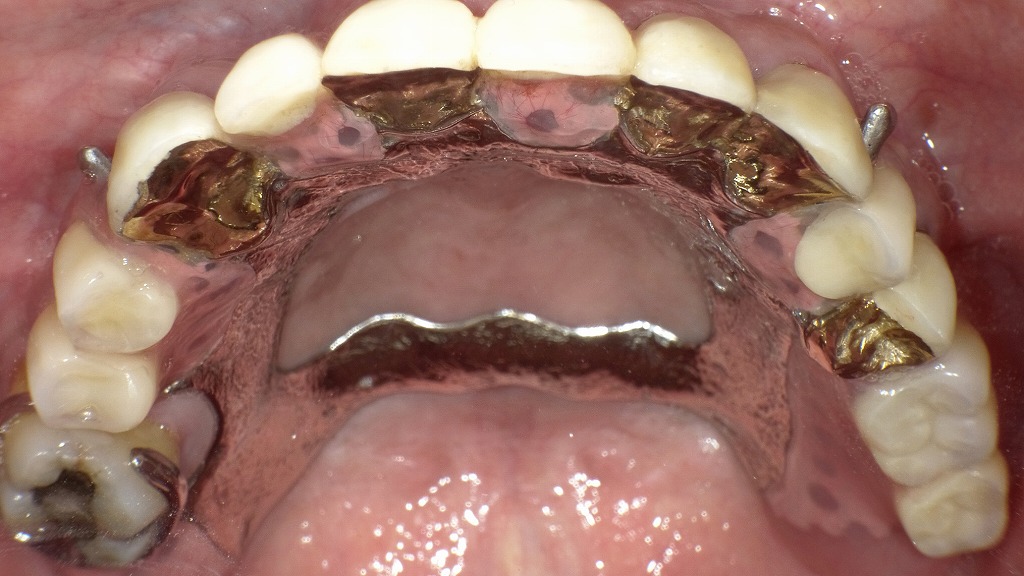

🔸 内冠装着時(治療途中)

上顎の支台歯に金合金製の**内冠(インナーコーヌス)**を装着した状態です。

それぞれの内冠は円錐形に形成されており、将来的に外冠が摩擦力でぴったりはまるよう精密加工されています。

- 内冠はすべて平行性を保って設計されており、

義歯の着脱がスムーズで安定感が高まります。 - 支台歯をしっかり保護し、将来的な歯の動揺を防ぐ効果もあります。

咬合面から見ると、**金属床(メタルフレーム)**が確認できます。これは義歯全体の強度と薄さを両立させるために用いられています。